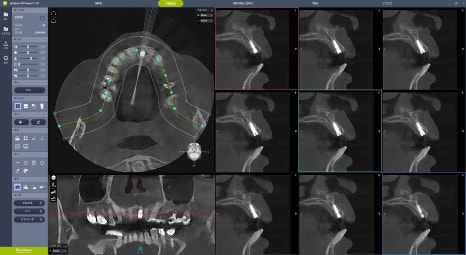

3차원 분석을 위한 Dentium CT 촬영을 통해 수술 계획을 원장이 직접 수립합니다. 공장형 치과에서는 오늘 누가 어디에 몇 개 임플란트를 심는지 수술방에 가서야 확인하는 경우도 있습니다. 우리는 언제나 원장이 직접 진단하고 상담, 수술 및 보철 수복 계획까지 직접 세우기 때문에 환자 개개인에 맞게 충분한 고민 후에 수술에 임할 수 있습니다.

디지털 내비게이션은 치과의사의 편의를 위해 개발된 수술 가이드(guide)입니다. 디지털 내비게이션을 잘 다루기 위해서는 가이드 없이 진행하는 임플란트 식립 - 즉 프리핸드(free-hand) 수술 실력이 뒷받침 되어야 합니다. 우리 치과는 원장이 직접 프리핸드 수술 경험을 토대로 디지털 가이드 계획을 수립하는데, 이것은 모든 수술 과정을 의사가 직접 통제하고 책임지기 위함입니다. 원가이드, 디오나비 등 임플란트 회사 직원들에게 외주 맡겨 디자인한 가이드를 그대로 받아 사용하는 일은 없습니다.